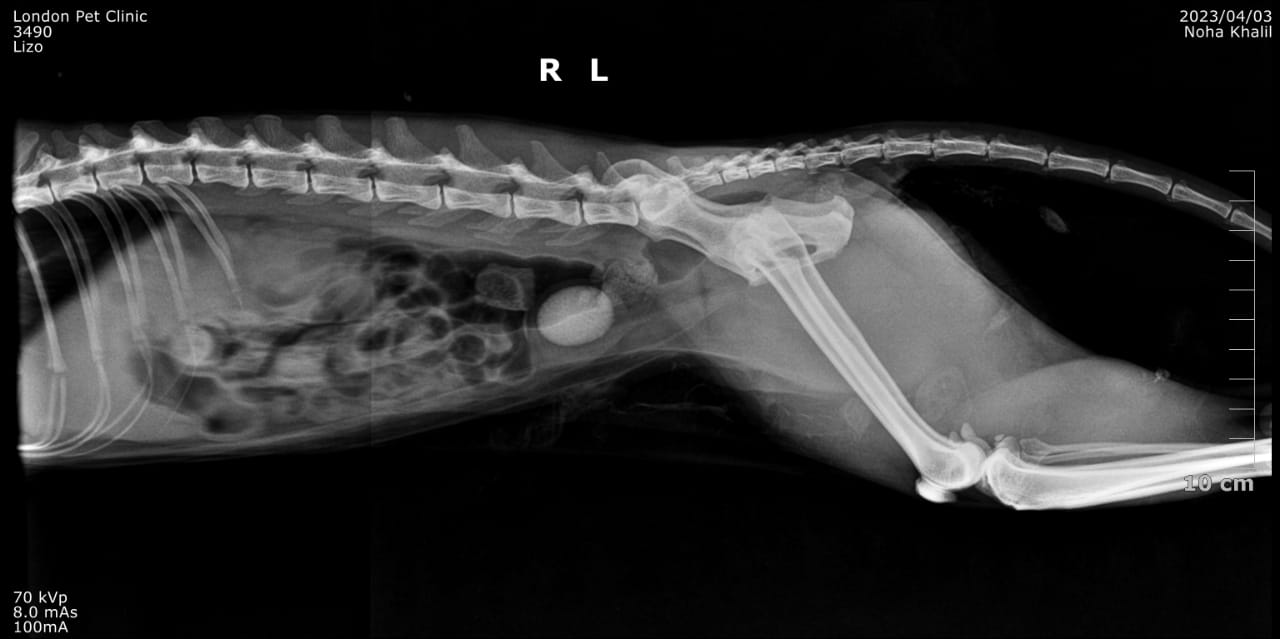

Abdominal Radiographs: Single large radiopaque urolith visible in the bladder

Ultrasound: Confirmed bladder stone, no evidence of renal involvement or ureteral obstruction